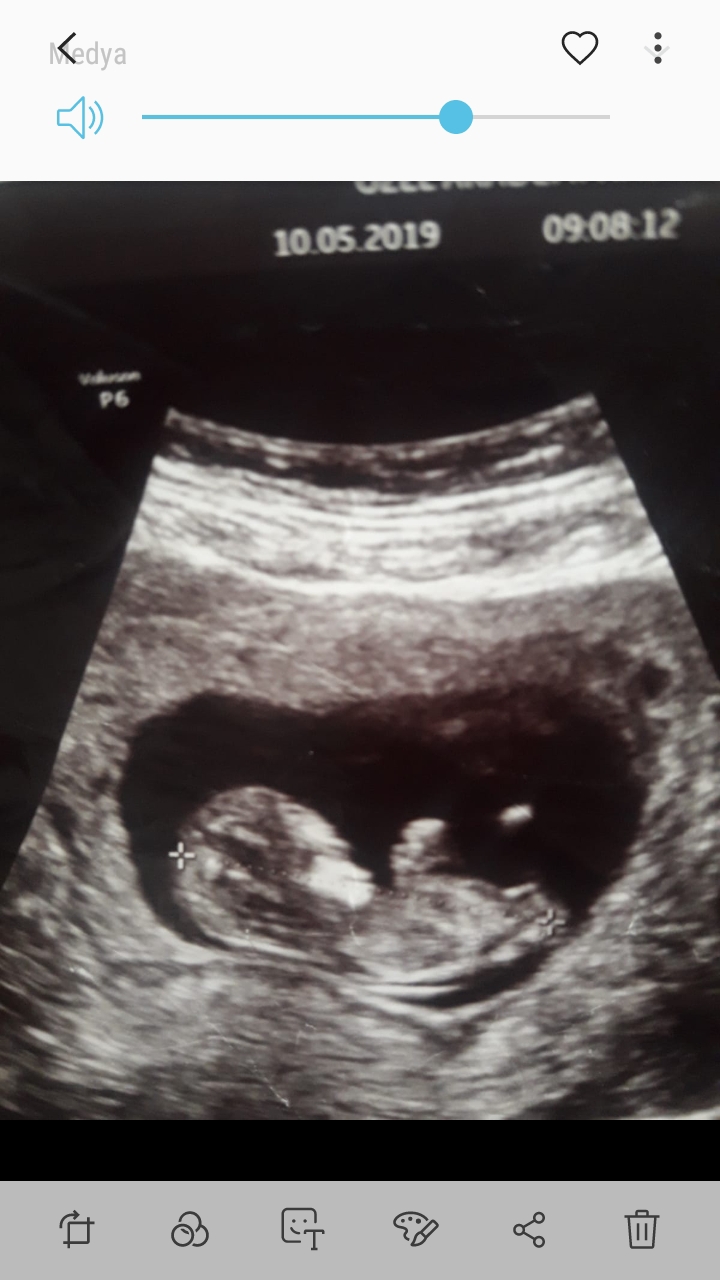

13+2 nub değerlendirir misnz acaba dr foto wermedi bunlar bnm çektiğm fotolar